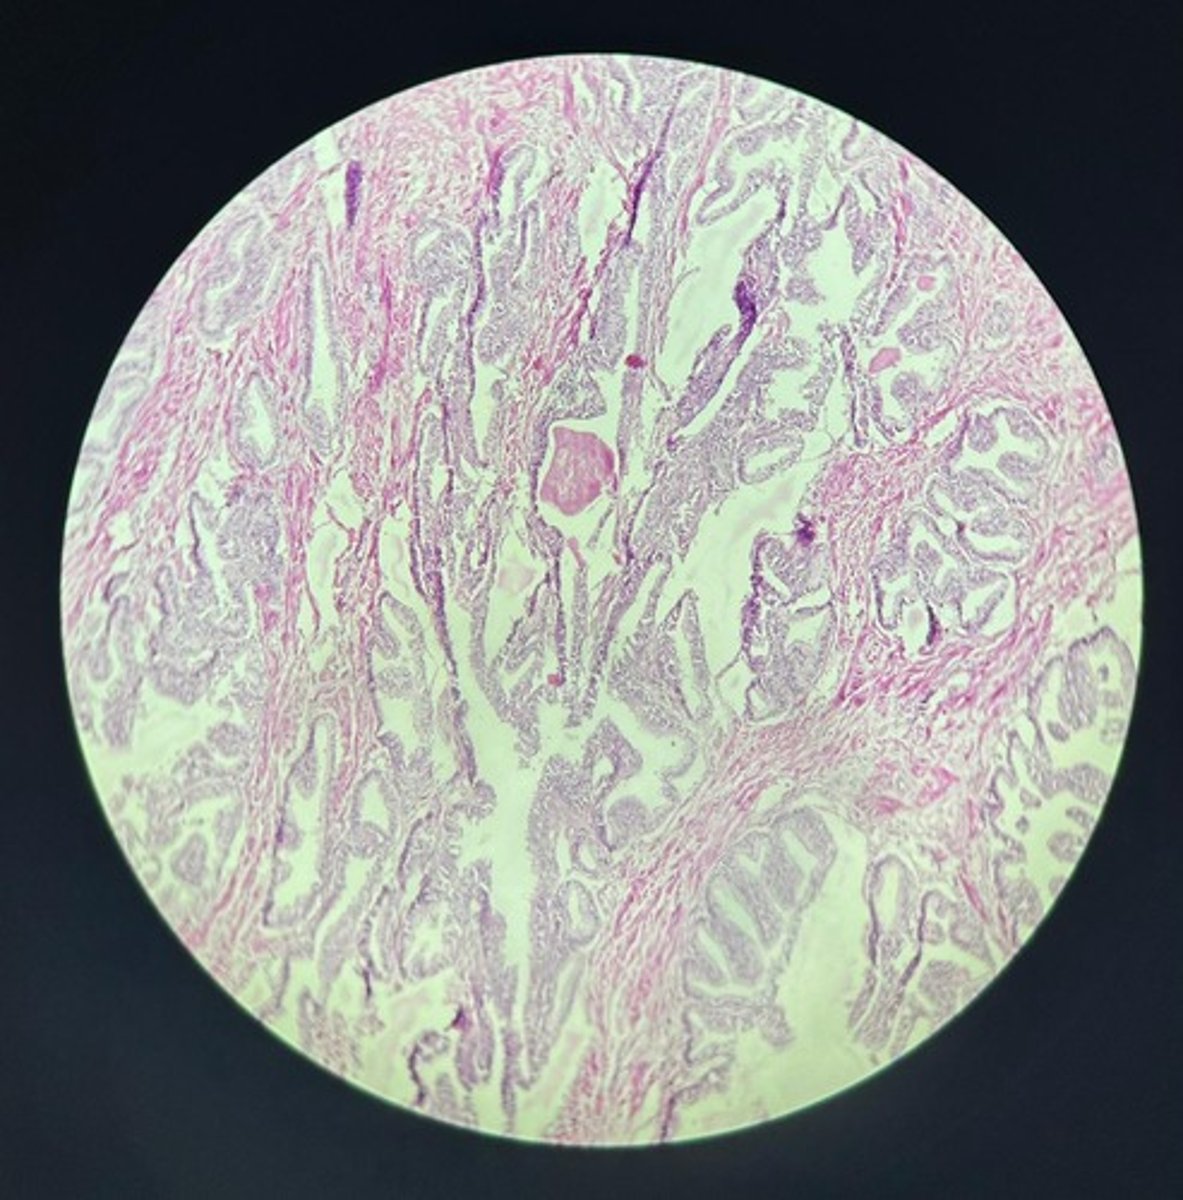

Uterus HE

Uterus HE

Uterus HE

Uterus HE